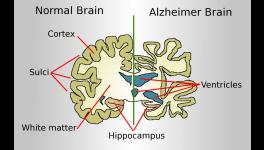

It also reinforces the fact that quality of sleep is related to the development of dementia, like Alzheimer’s disease. In the pathological condition of Alzheimer’s disease, the ability of the brain to remove toxic proteins like amyloid beta or tau fails and these toxic substances accumulate in the brain. With the progression of age, sleep often becomes increasingly lighter and disruptive. This study also potentially explains the links between aging, sleep deprivation and risk of Alzheimer’s disease.

It is only very recently that any information about the cleaning mechanism adopted by the brain came to be known. It was in 2012 when Nedergaard—the lead author of the study we are discussing, and his team discovered how the brain cleans the toxic out of it. They named it the ‘Glymphatic System’. This unique system functions in a similar way where debris are removed by water using a hose pipe; with water getting replaced by CSF (cerebrospinal fluid) and the pipe by the perivascular channels. The perivascular space in the brain are the tiny spaces between the veins, arteries and the pia mater—the delicate inner most part of the meninges, the protective surrounding of the brain and the spinal cord.

The glymphatic system removes soluble proteins and metabolites from the central nervous system. It is also involved in distribution of compounds like glucose, lipids, amino acids and neurotransmitters in the brain.

Interestingly, the glymphatic system becomes active during sleep and remains largely non-engaged during the period of wakefulness. This says that sleep is not shutting down of the brain; rather, sleep is another state the brain needs to be in for the waste removal system to be active. Since its discovery, plethora of researches have shown that the functioning of the glymphatic system gets suppressed in several diseases and this failure of the system in turn helps in developing neurodegenerative diseases, traumatic brain injury and also stroke.